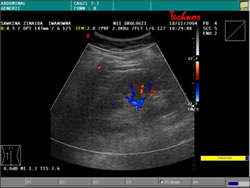

УЗИ: |

|